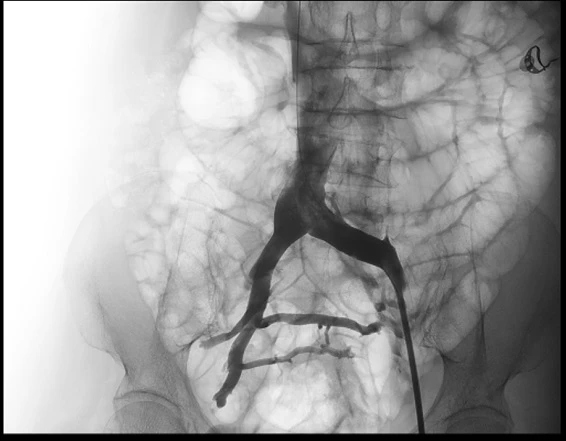

Tại đây, các bác sĩ khoa Lồng ngực mạch máu của BV đã chẩn đoán bệnh có nguồn gốc từ hội chứng chèn ép tĩnh mạch chậu và tắc mạch huyết chân, cần phải điều trị tải thông mạch máu. Sau đó bà G. được nong bóng và đặt stent vào tĩnh mạch chậu, tải thông dòng máu về tim.

Các bác sĩ khoa Lồng ngực mạch máu, BV ĐH Y Dược chẩn đoán bệnh nhân bị suy tĩnh mạch giai đoạn cuối do hội chứng chèn ép tĩnh mạch chậu. Bà H. cũng được điều trị bằng nong bóng và đặt stent tải thông tĩnh mạch chậu thành công.

Theo ThS-BS Lê Thanh Phong, trước đây hội chứng chèn ép tĩnh mạch chặn được điều trị bằng phẫu thuật, rất phức tạp, mất nhiều máu và gây đau đớn. Ngày nay, với sự phát triển của can thiệp nội mạch, hội chứng này có thể điều trị khỏi bằng cách nong bóng và đặt giá đỡ tĩnh mạch (stent) chỉ qua một vết đâm kim vùng bẹn đùi. Người bệnh có thể đi lại vài giờ sau mổ và có thể xuất viện trong ngày.